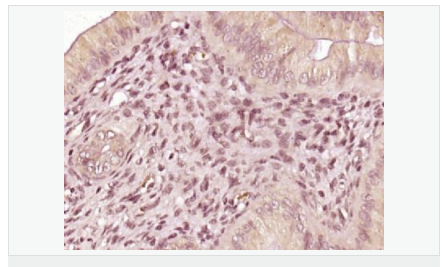

| 產品應用 | ELISA=1:5000-10000 IHC-P=1:100-500 IHC-F=1:100-500 Flow-Cyt=1μg/Test ICC=1:100 IF=1:100-500 (石蠟切片需做抗原修復) not yet tested in other applications. optimal dilutions/concentrations should be determined by the end user. |

| 細胞定位 | 細胞核 細胞漿 |